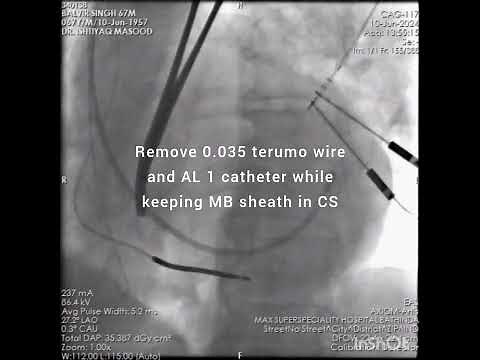

CRT D Implantation (step by step)

YouTube

Dr Ishtiyaq Masood

已浏览 2716 次

2024年9月9日